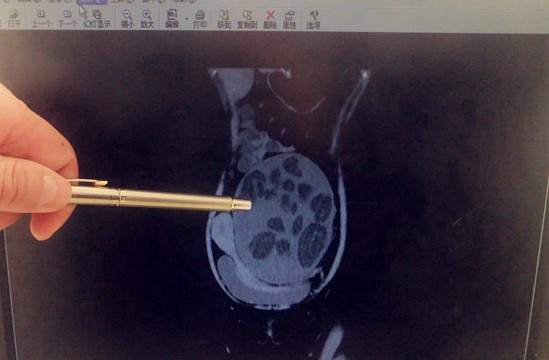

房燕的腹腔明显被畸胎瘤填满

11月29日消息房燕(化名)是一位年仅25岁的单身女性,但前段时间她的腹部却像孕妇般一天天隆起,让人匪夷所思。经青岛市立医院妇科确诊,房燕患了巨大腹膜后畸胎瘤。10月11日市立医院妇科为房燕成功实施了肿瘤切除手术,切除的肿瘤相当于一个儿童用足球大小。